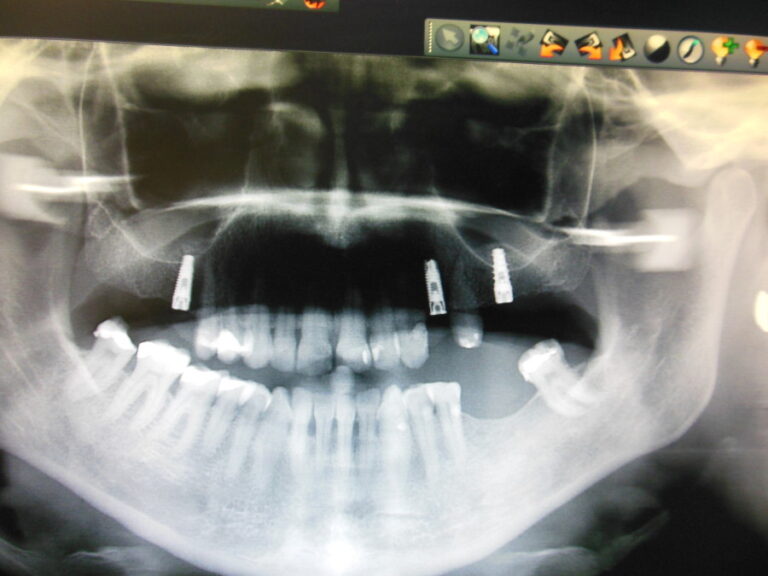

Ortodoncja CBCT

Leczenie chirurgiczno-ortodontyczne wad zębowych z zastosowaniem tomografii spiralnej CBCT w naszej klinice.